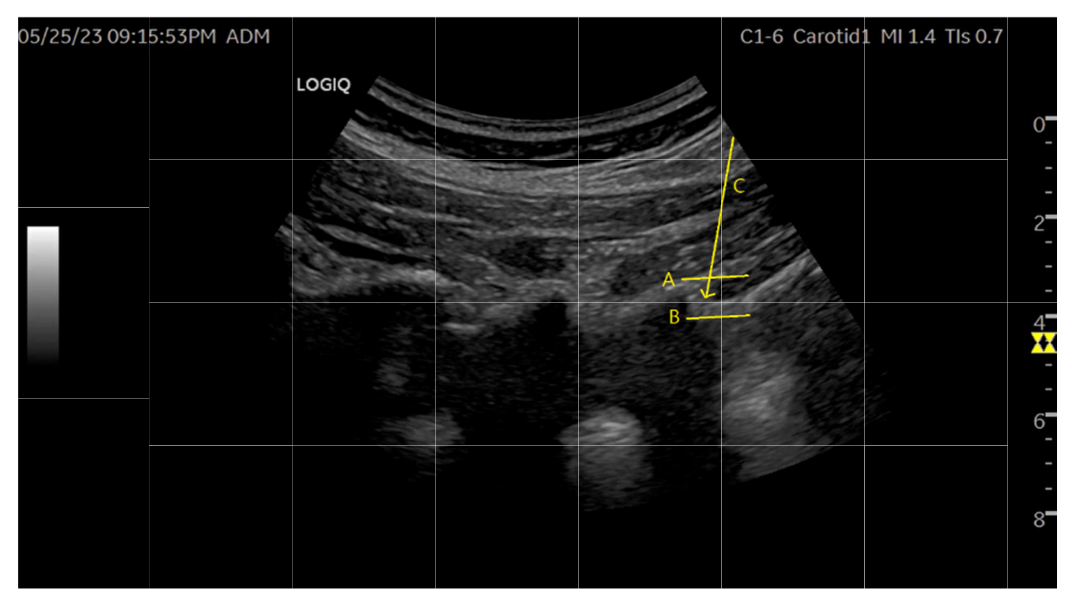

③ 침도 자입 시 Probe의 간섭을 피하기 위해 초음파에서 1cm 정도 떨어진 위치의 수평면상에서 15도 정도 침도를 기울여 자입한다.

④ 시술하려는 레벨의 위 라미나의 상단에서 하단 사이를 목표로 초음파상에서 진입경로를 확인한다.

⑤ 에피듀라에 진입하지 않고, 황색인대를 안전 자극할 수 있는 골표지자(Bone turnover marker)는 위 라미나의 하단과 아래 라미나의 상단 사이다.

⑥ 시술 목표에 따라 황색인대를 Epidural space에 진입하지 않는 선에서 초음파 중재 하에 절개한다.

연구진은 이때 가장 주의할 점으로 경막 자극 및 경막 천공 손상을 꼽았는데, 경막 자극을 피하기 위해선 황색인대 침도 시술 시 완전히 관통시키지는 않아야하며, 이를 위해 자입심도를 초음파로 확인해 해당 깊이 이상 침도를 진침 시키지 않도록 권고했다.

“정확한 침도 시술을 위한 초음파의 보조적 요법 프로토콜”

연구진은 “시술 결과 초음파 유도 하 침도 시술은 축자입을 하기 때문에 침도가 진입하는 전장과 침 끝을 놓치지 않고 시술할 수 있었으며, 각도를 눕혀서 하는 일반적인 In plane 시술에 비해 더 적은 침습으로 시술이 가능했다”면서 “장비의 성능과 시술자의 숙련도에 따라 침도날의 끝을 정확히 확인하며 진입하는 것이 중요하다”고 강조했다.